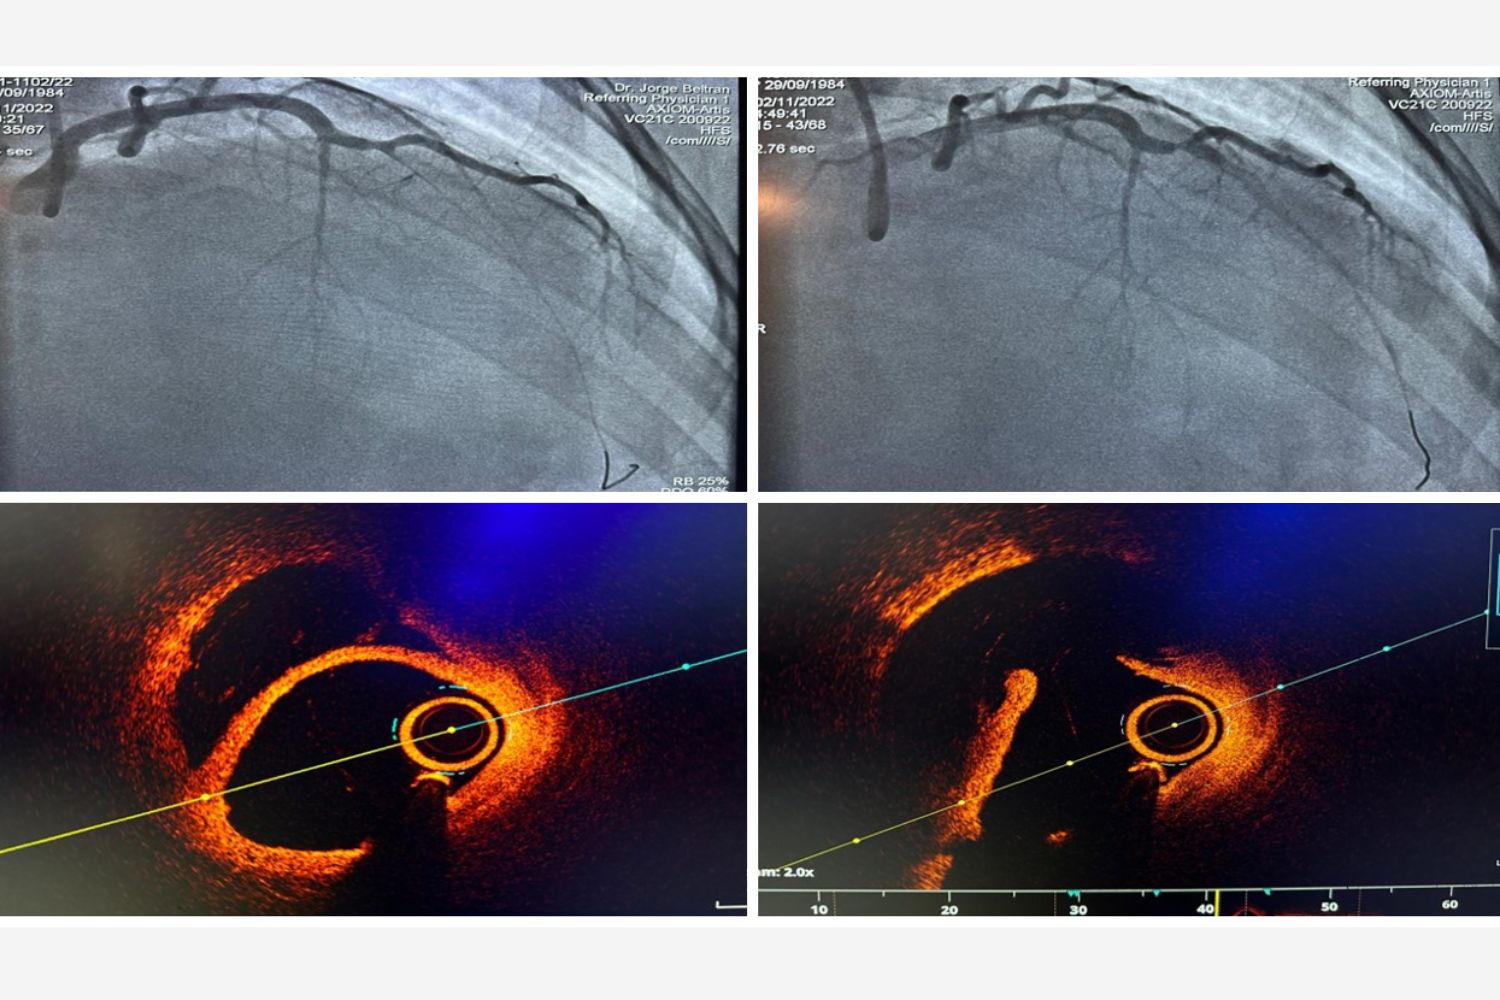

Image of the Week - 22 October 2025

Doctor Nur Rahma Almaraz

Doctor Elena Sufrate Sorzano

Miss Teresa Gonzalo Moreno